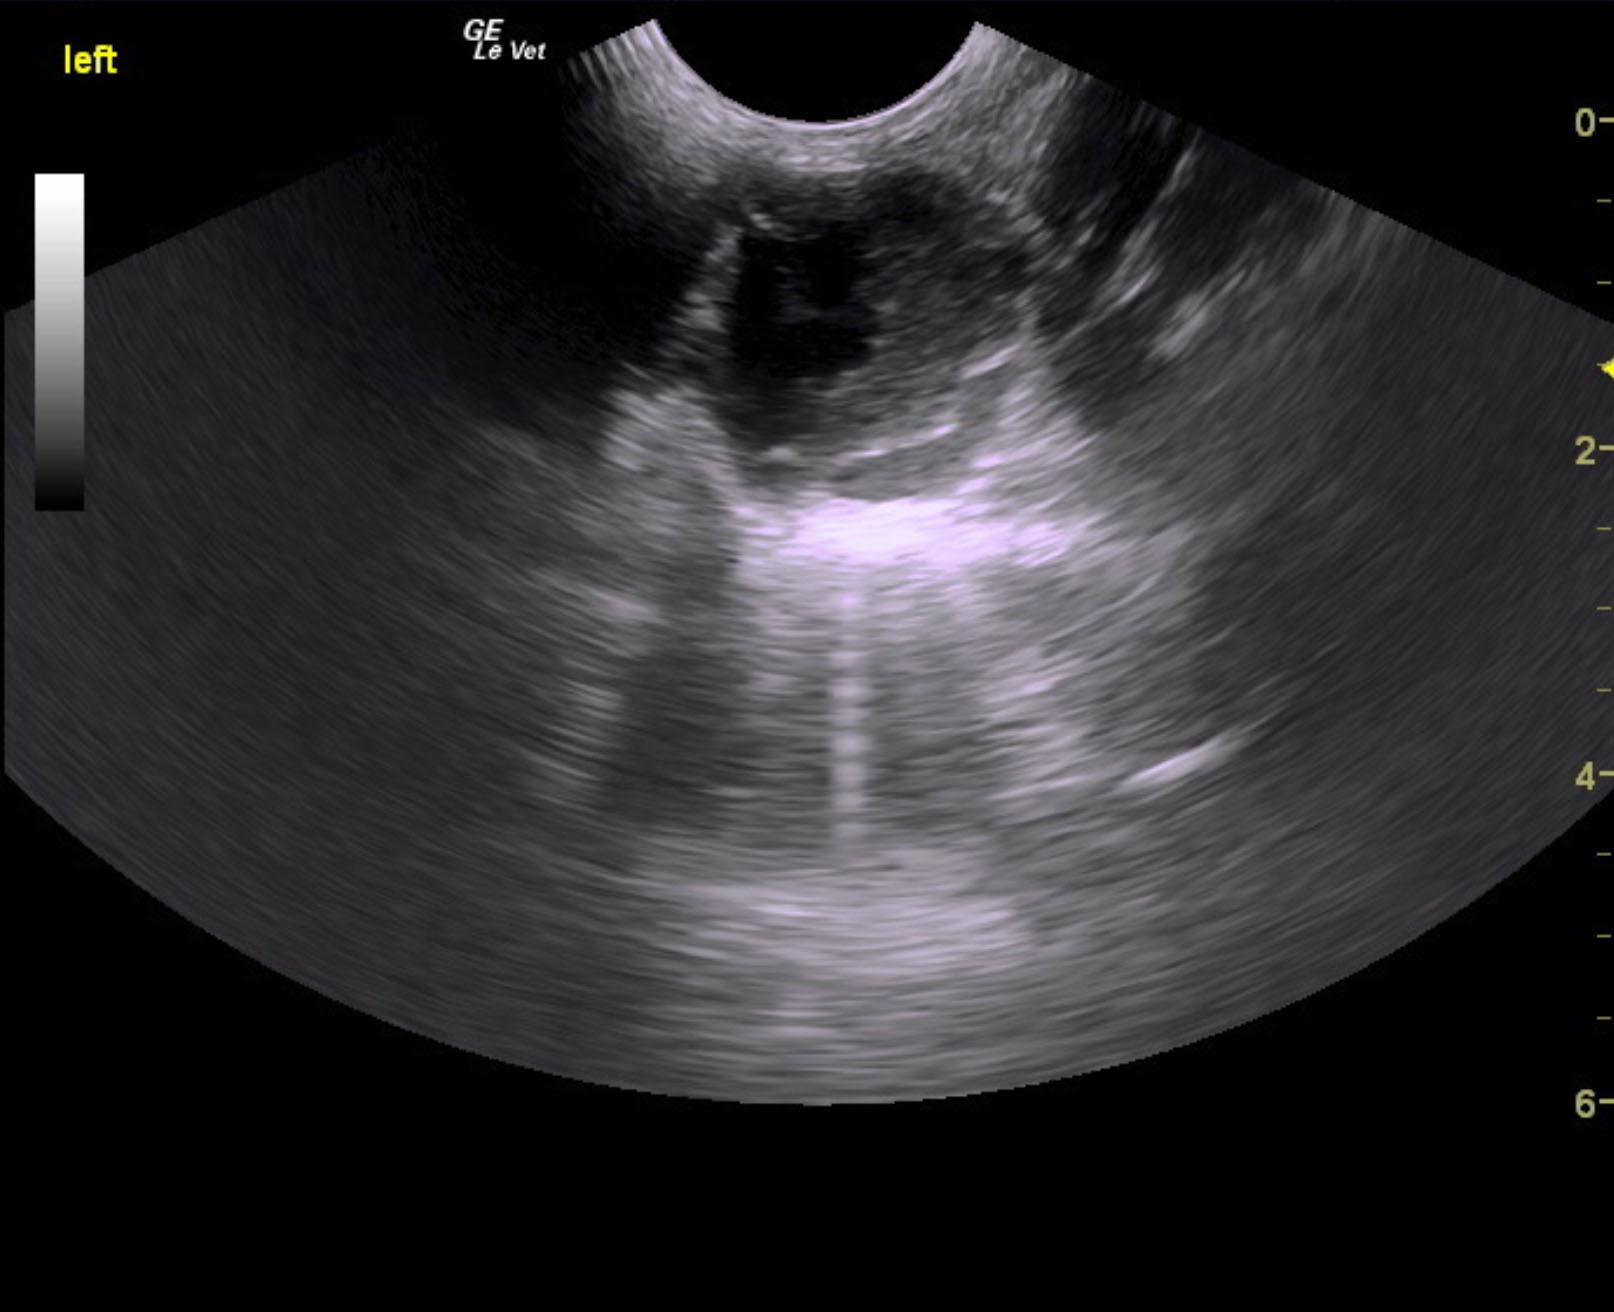

An 11-year-old NM Schnauzer was presented for evaluation of a possible eye tumor and splenic mass. On physical examination, left ocular pressure was increased. CBC showed mild anemia and on survey radiographs possible splenic mass and bladder stones were evident.